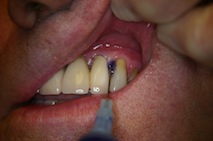

FotoSan 360

Přístroj na principu světlem aktivovaná desinfekce neboli fotodynamická antimikrobiální chemoterapie. Přístroj s okamžitým účinkem ničí veškeré mikroorganismy bez jakýchkoli vedlejších účinků. Jedná se o bezbolestné ošetření, které nevyžaduje anestezii, nemá vedlejší účinky a ničí 99% bakterií. Používá se především v parodontologii a implantologii při léčbě zánětů v okolí zubů a implantátů (dezinfekce tzv. chobotů), záchovné stomatologii (ošetření kazů) i endodoncii (dezinfekce kanálků zubu).